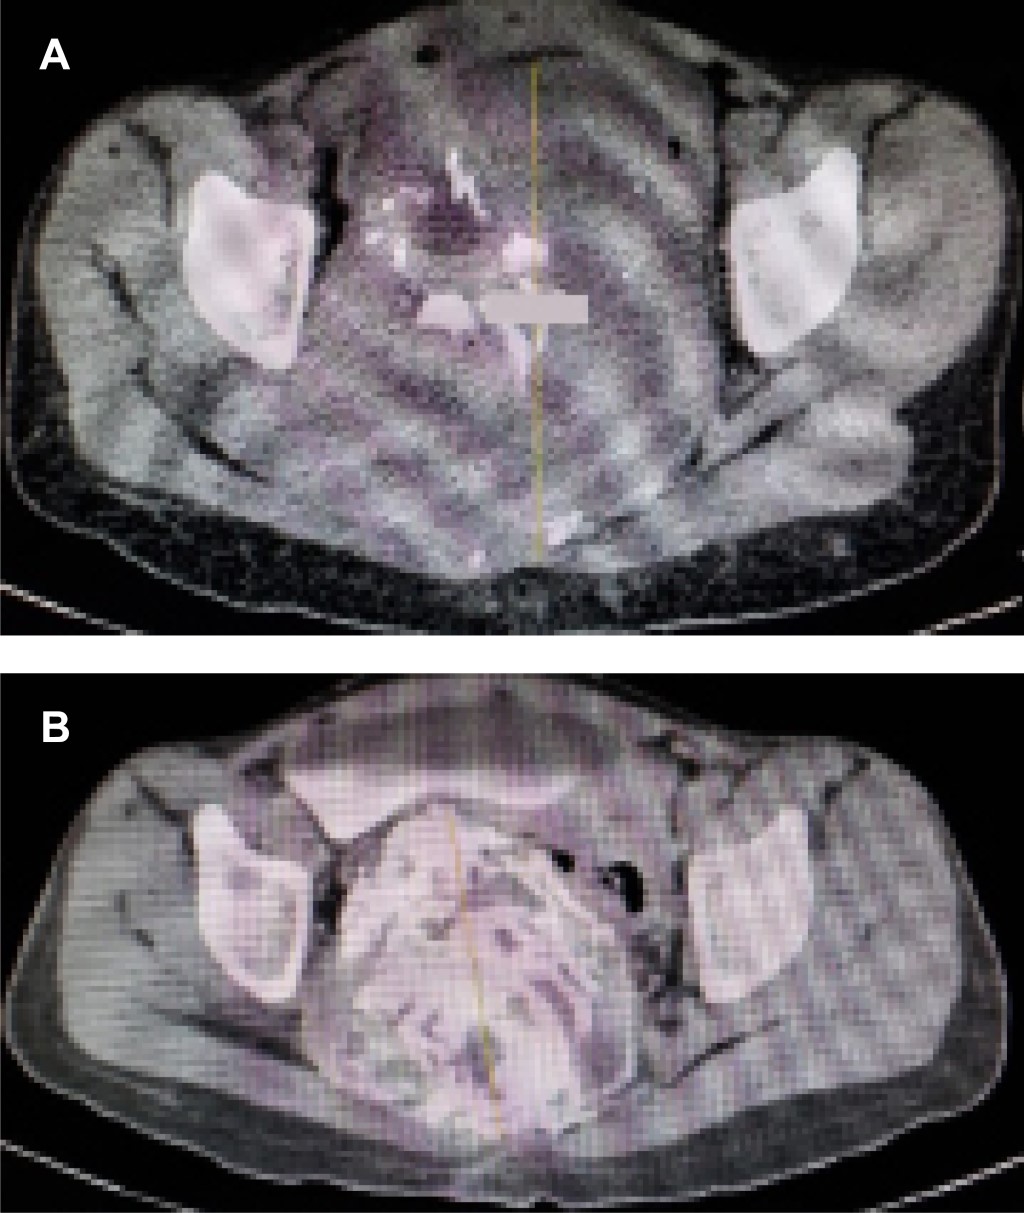

Paciente femenino de 21 años, sin antecedentes heredofamiliares de importancia; menarca a los 12 años, eumenorréica, inicio de vida sexual activa (IVSA) 18 años, parto 1, para 1. Referida al servicio de ortopedia por presentar, en un lapso de tres meses, pérdida progresiva de control de esfínteres, retención urinaria, incapacidad para la marcha, dolor y distensión abdominal. Se realizó ultrasonido abdominopélvico, el cual reveló masa tumoral intrapélvica. Se completaron estudios de tomografía computarizada y gammagrama óseo con 99mTc-MDP (Figura 1) y se efectuó biopsia de sacro, el reporte histopatológico confirmó tumor de células gigantes (TCG) de dicho hueso. Se inició tratamiento utilizando denosumab 60 mg/mes, completando ocho dosis. La evolución fue hacia la mejoría clínica, con desaparición de dolencia y parestesias, recuperación del dominio de esfínteres y marcha con ayuda de andador, el estudio de imagen de control mostró reducción de tamaño tumoral, de inicialmente 452 mm, a 98.7 mm (Figura 2).

Figura 2